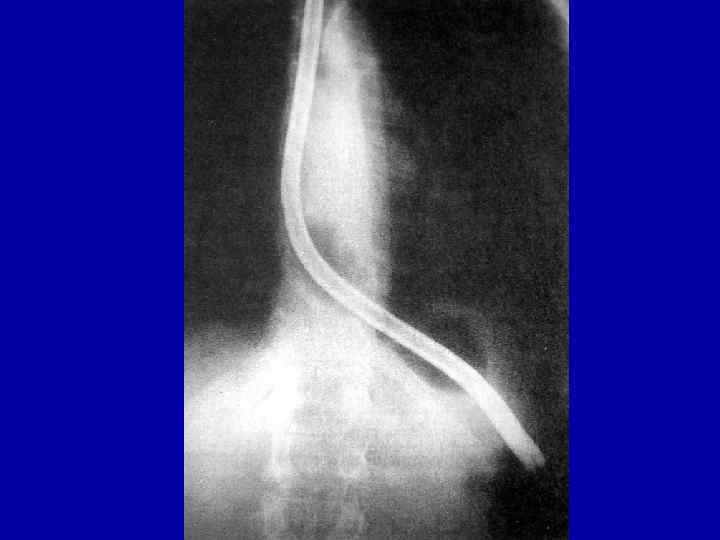

Кардиоспазм 3 степени

Больная К. , 56 л. Ds: кардиоспазм IV стадии 10. 09. 03 – экстирпация пищевода с одномоментной пластикой желудочной трубкой